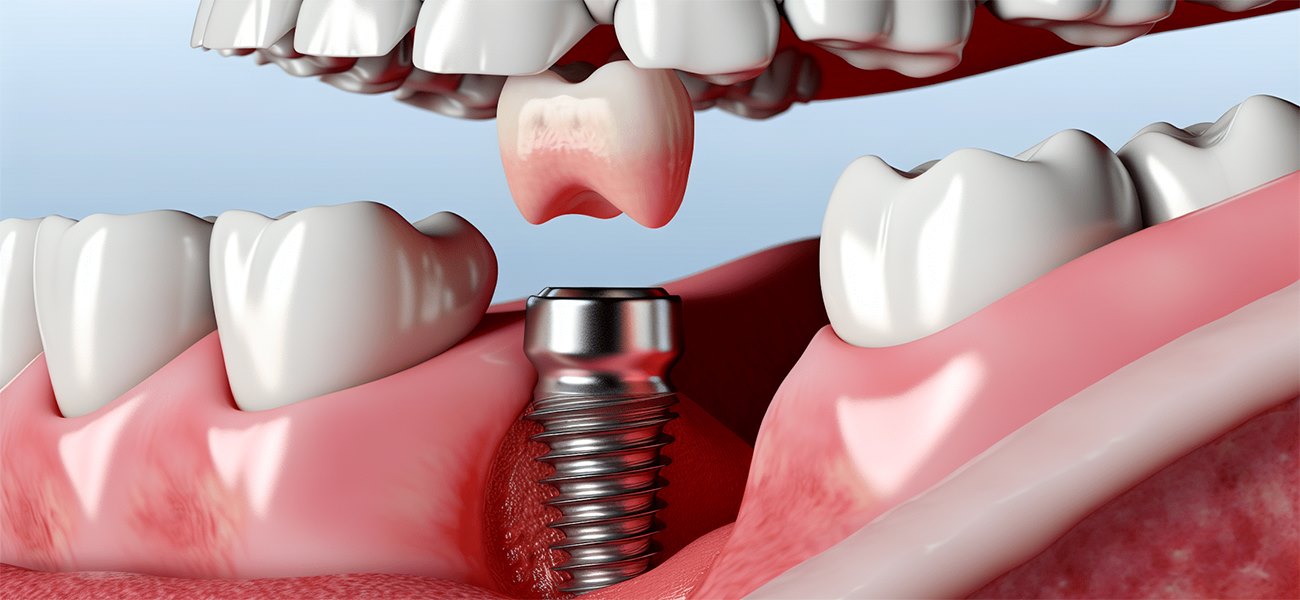

ایمپلنت دندان یکی از پیشرفتهترین و موثرترین روشهای درمانی برای جایگزینی دندانهای از دست رفته است. این روش به دلیل مزایای فراوانی که دارد، به سرعت در حال محبوبیت یافتن است. با این حال، انتخاب یک کلینیک معتبر و متخصص برای انجام این عمل بسیار حائز اهمیت است. در این مقاله، به معرفی کلینیک تخصصی ایمپلنت دندان دکتر مهسا فربد در سهروردی خواهیم پرداخت و به بررسی خدمات، تکنیکها و مزایای این کلینیک خواهیم پرداخت.( دکتر مهسا فربد فلوشیپ ایمپلنت از فرانسه, بهترین کلینیک تخصصی ایمپلنت دندان )

- ایمپلنتهای دندانی

- مرحله سوم: انجام عمل ایمپلنت

عمل ایمپلنت تحت بیحسی موضعی یا عمومی انجام میشود. پزشک با استفاده از تکنیکهای پیشرفته، پایه ایمپلنت را در استخوان فک قرار میدهد.

- مرحله چهارم: دوره بهبودی

پس از انجام عمل ایمپلنت، بیمار باید دورهای را برای بهبودی سپری کند. در این مدت، پایه ایمپلنت با استخوان فک ادغام میشود.

- مرحله پنجم: نصب پروتز

پس از اتمام دوره بهبودی، پروتز دندانی بر روی پایه ایمپلنت نصب میشود تا بیمار بتواند عملکرد طبیعی خود را بازیابد.